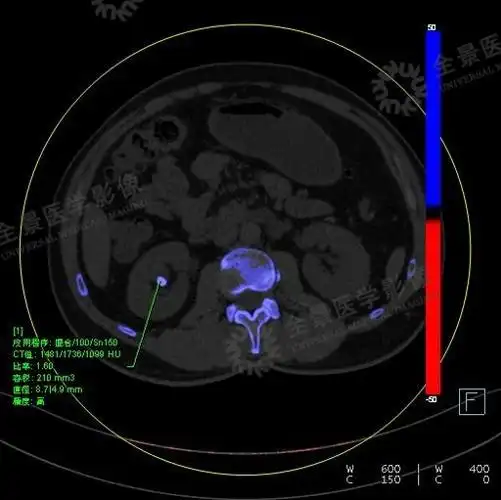

双能量ct可将尿酸结石和其他类型的肾结石区分开来:后处理结果会显示